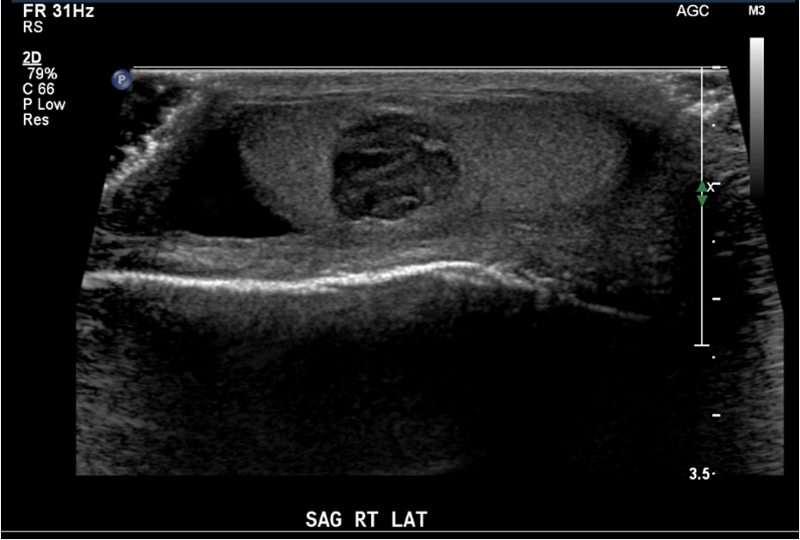

fever

scrotal pain

swelling

untreated orchitis

Testicular abscess